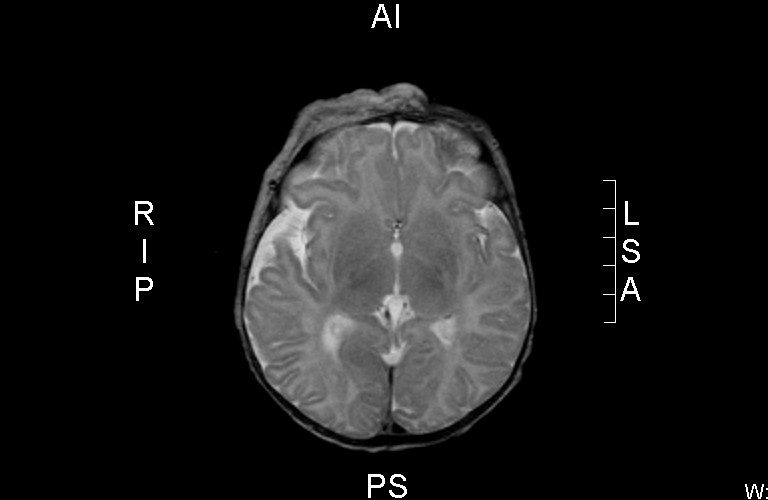

![Dandy-Walker malformatie (click on photo to enlarge) [source: www.huidziekten.nl] Dandy-Walker malformatie](../../../images/Dandy-Walker-malformatie-3z.jpg) |

Dandy-Walker malformatie |

MRI:

Beeld van hemangioom

in de cutis rechts parietaal en frontaal, doorlopend in de rechter orbita.

Hypoplasie van de vermis en de rechter cerebellum hemisfeer met wat wijde

achterste schedelgroeve, gevuld met liquor - beeld passend bij een

Dandy-Walker malformatie.